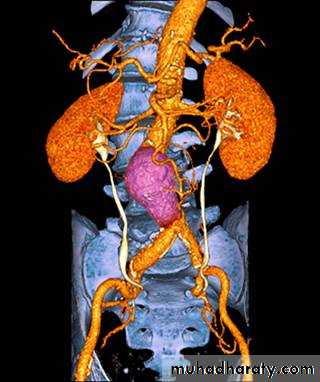

CT & CT angio of abdominal aortic aneurysm

Ruptured abdominal aortic aneurysm